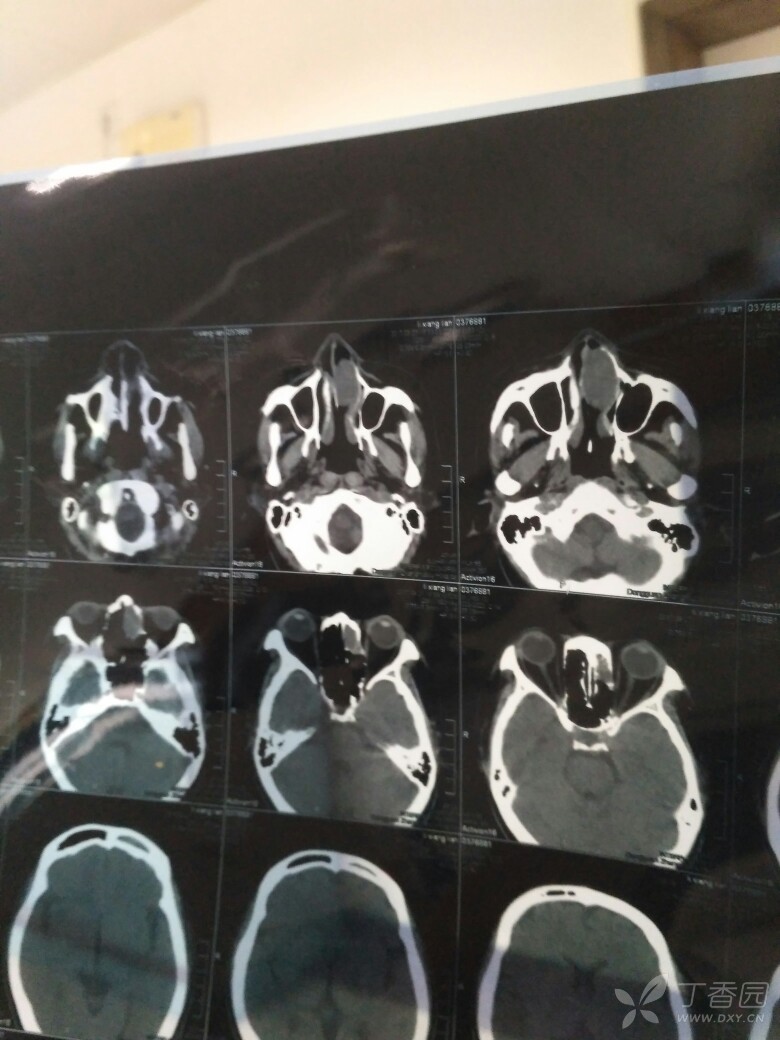

双侧上颌窦炎,筛窦炎,额窦炎ct结果求助 1,主要病症:医院拍"鼻咽部ct